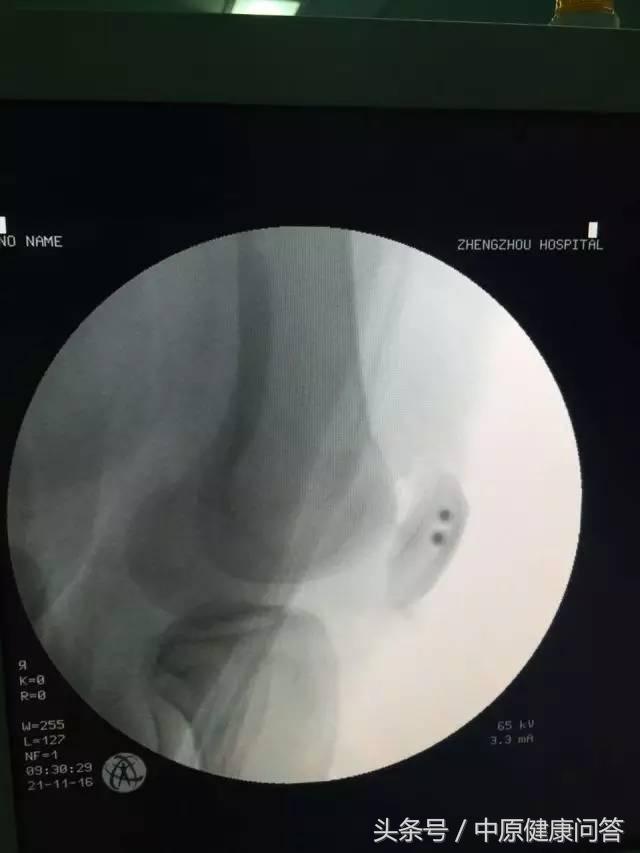

手术中

经过了充分的准备,在骨科三病区团队精心配合下,小芳的手术十分成功,10天后小芳就已经出院,虽然术后仍然要固定6-8周,术后3个月之后还需要复查并进行功能锻炼。

术后复查